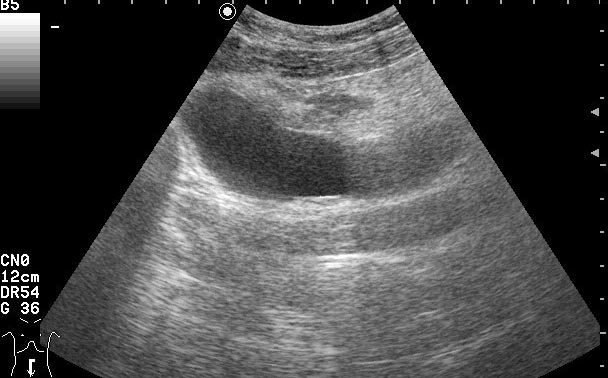

УЗИ - Воспаление урахуса

Женщина 42 лет с болями внизу живота, дизурическими явлениями, повышением температуры.

Сонограммы мочевого пузыря

, в случае обнаружения образования в области верхушки мочевого пузыря, я должна думать о патологии урахуса.

Похоже на опухоль, но по анамнезу я больше склоняюсь к воспалению урахуса!

Согласна с первым постом-возможно нагноение урахуса(и клиника подходит)